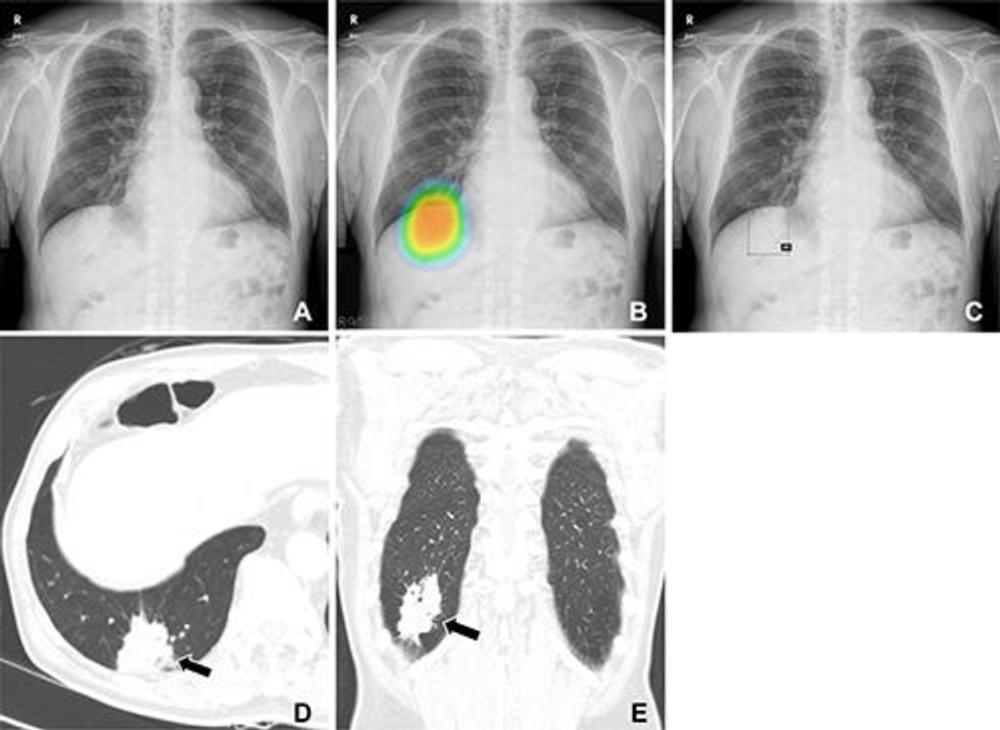

Figure 3. (A–C) Chest radiographs obtained as part of a health checkup in a 71-year-old male patient show reader susceptibility to high diagnostic accuracy artificial intelligence (AI). In the first session without AI, a thoracic radiologist with 16 years of experience read the chest radiograph as a normal radiograph (A) . High diagnostic accuracy AI observed potential lung cancer in the radiograph with an 89% CI as indicated by the nodule localization map (B) (as the color changes from blue to red, the probability of the presence of a nodule increases). When presented with the AI suggestion at the second reading session, the radiologist changed the decision and annotated lung cancer in the area that overlapped with the right hemidiaphragm (box annotation) (C) . (D, E) Contrast-enhanced chest CT scans show a 6.8-cm lung mass (arrow) with an air bronchogram in the right lower lobe in the axial (D) and coronal (E) planes. This mass was pathologically proven to be an invasive mucinous adenocarcinoma. Therefore, the reader’s decision was incorrect in the first session but correct in the second session after following the AI suggestion.

High-res (TIF) version